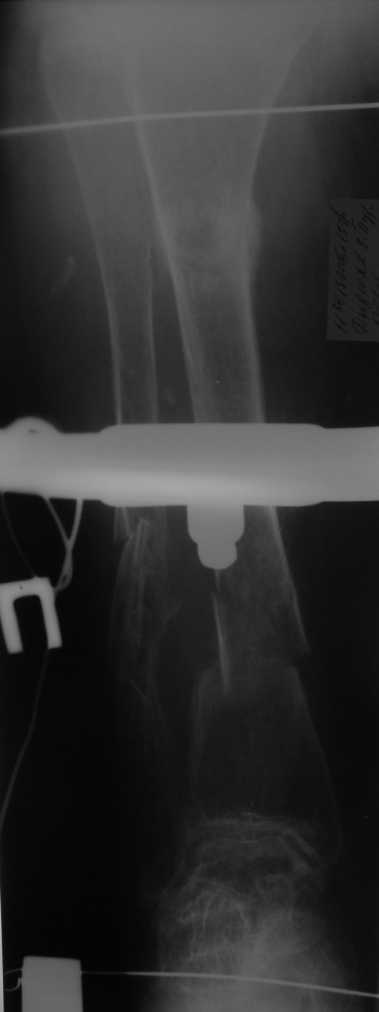

Но даже при малоинвазивной методике лечения применимой для даной больной существуют следующие проблемы: выраженный остеопороз, тонкий кортикал, очень широкий канал.

Контрольные рентгенограммы прилагаю.

Проблема в том, что в сагитальной плоскости угол голеней =30 градусам. Ширина канала 30.